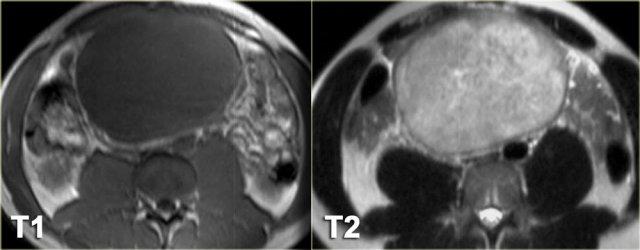

Hình bên trái là bệnh nhân nam 33 tuổi than phiền về tình trạng bụng ngày càng to, cảm giác đầy bụng và sờ thấy khối ở bụng.

Trước tiên hãy nghiên cứu các hình ảnh bên trái rồi tiếp tục xem hình MRI.

Hãy tìm các đặc điểm hình ảnh hữu ích trong chẩn đoán phân biệt.

Trước hết, đây là tổn thương có bờ rõ với giảm tỷ trọng trên CT.

Có ngấm thuốc nhẹ xung quanh tổn thương và một số dải ngấm thuốc nhỏ bên trong tổn thương.

Trên MRI, tổn thương giảm tín hiệu trên chuỗi xung T1W như dự kiến.

Trên chuỗi xung T2W, tổn thương tăng tín hiệu tương đối.

Kết hợp với giảm tỷ trọng trên CT, điều này cho thấy có chứa mucin bên trong tổn thương.

Đặc điểm này rất gợi ý chẩn đoán u xơ mạc treo.